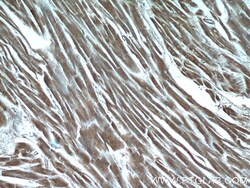

Supportive validation

- Submitted by

- Invitrogen Antibodies (provider)

- Main image

- Experimental details

- Immunohistochemistry of paraffin-embedded human heart tissue slide using 16180-1-AP (MYPN-Specific Antibody) at dilution of 1:50 (under 10x lens).